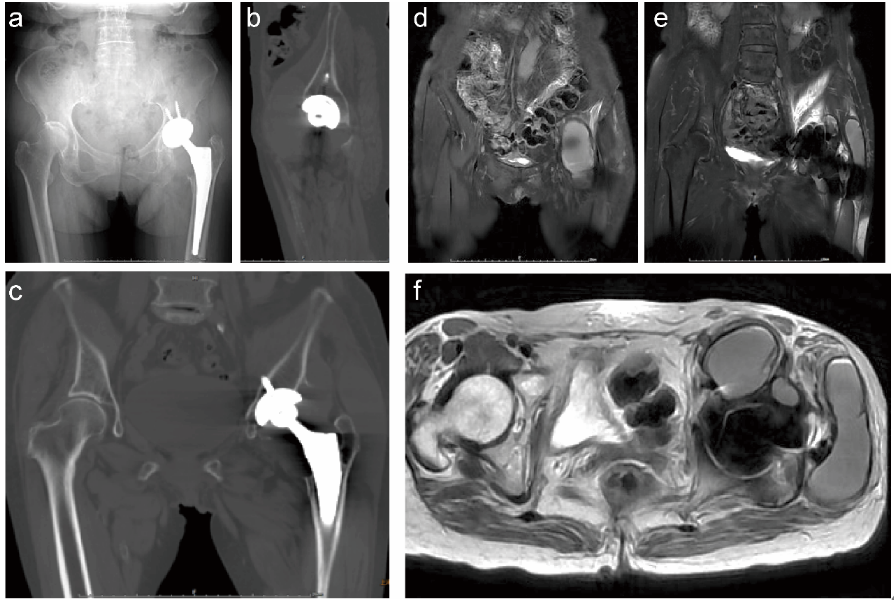

她来到附属瑞金医院骨科后,何川主任医师先通过详尽病史询问和体格检查初步判断,随后安排实验室检查,结果显示炎症标志物、凝血功能均无异常,关节滑液细菌培养也呈阴性;医生没有停下排查的脚步,紧接着安排了X光片和CT检查,影像片上小转子周围的骨溶解现象清晰可见。“常规影像只能看到骨组织的异常,但没法明确周围软组织的情况。”随后,减伪影磁共振成像(MRI) 检查显示T1、T2加权像呈现特殊信号混合影。

经过病理科、放射科和软组织肿瘤专科医生联合会诊,陈阿姨被确诊为全髋关节置换术(THA)后罕见的慢性扩展性血肿(CEH)。随后,何川主任医师团队为陈阿姨实施了肿块完整切除术,术中确认股骨侧假体完好固定,仅对髋臼侧进行翻修。如今,陈阿姨已完全康复,走路、爬楼都恢复正常,无任何复发迹象。“多亏找到了病根,再拖下去骨头可能要彻底坏了。”陈阿姨感慨道。